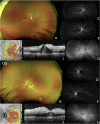

Purpose: Although conjunctivitis represents the most common ocular manifestation of COVID-19 infection, sight-threatening retinal involvement has been reported. Herein, we report and characterize with multimodal retinal imaging 5 cases of acute vision loss secondary to presumed chorioretinal vasculopathy temporally associated with COVID-19 infection with varying severity, visual morbidity, and treatment response, and review the available literature on the association between COVID-19 infection and retinal microvascular changes.

Results: 10 eyes of 5 patients, 3 men and 2 women, with a mean age of 30.8 years (median 33, range 16-44) were described. All patients had a recently preceding episode of COVID-19, with symptomatology ranging from mild infection to life-threatening encephalopathy. Treatment for their retinal disease included topical, oral, intravitreal, and intravenous steroids, steroid-sparing immunosuppression, retinal photocoagulation, antivirals, and antiplatelet and anticoagulant agents. Treatment response and visual recovery ranged from complete recovery of baseline acuity to permanent vision loss and need for chronic immunosuppression.

Conclusions and importance: Clinicians should be mindful of the potential for vision-threatening retinal involvement after COVID-19 infection. If found, treatment with both anti-inflammatory therapy and anticoagulation should be considered, in addition to close monitoring, as some patients with this spectrum of disease may require chronic immune suppression and/or anti-VEGF therapy.